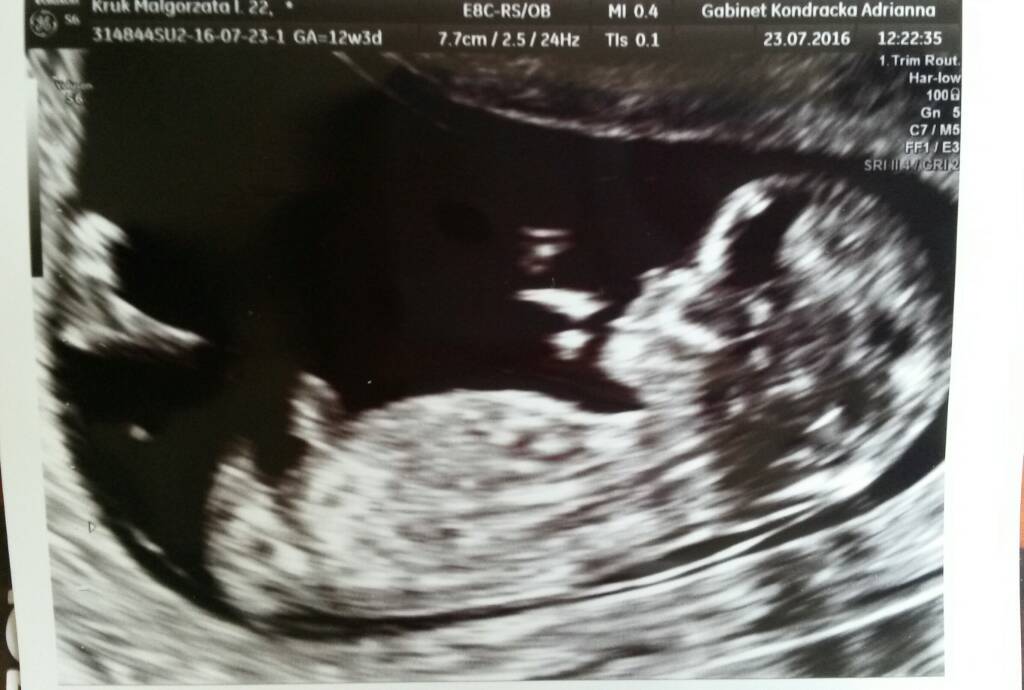

Moje słoneczko ma 6cm :) wszystkie pomiary bardzo dobrze wręcz idealne :) z tego usg wychodzi 12t3d czyli 2 dni do przodu i termin wyrównał mi się z terminu z om na 1.02 :) stopka ma już 1cm :) płci Pani doktor nie chciała mówić, bo mówiła że teraz może być równie dobrze przerosnieta lechtaczka lub już penisek ;) i jeśli bardzo będzie nas korcić to możemy sprawdzić w 16 tygodniu,także nadal każde może upierac się przy swoim ja mam synia, Kamil corcie ;) Doktor przemiła, wszystko nam tłumaczyła, o dziecku mówiła już jak o małym czlowieczku, a nie plodzie, super się u niej czuliśmy i na kolejne ważne usg na pewno będziemy chodzić do niej :)

Moje słoneczko ma 6cm :) wszystkie pomiary bardzo dobrze wręcz idealne :) z tego usg wychodzi 12t3d czyli 2 dni do przodu i termin wyrównał mi się z terminu z om na 1.02 :) stopka ma już 1cm :) płci Pani doktor nie chciała mówić, bo mówiła że teraz może być równie dobrze przerosnieta lechtaczka lub już penisek ;) i jeśli bardzo będzie nas korcić to możemy sprawdzić w 16 tygodniu,także nadal każde może upierac się przy swoim ja mam synia, Kamil corcie ;) Doktor przemiła, wszystko nam tłumaczyła, o dziecku mówiła już jak o małym czlowieczku, a nie plodzie, super się u niej czuliśmy i na kolejne ważne usg na pewno będziemy chodzić do niej :) Zobacz załącznik 764019